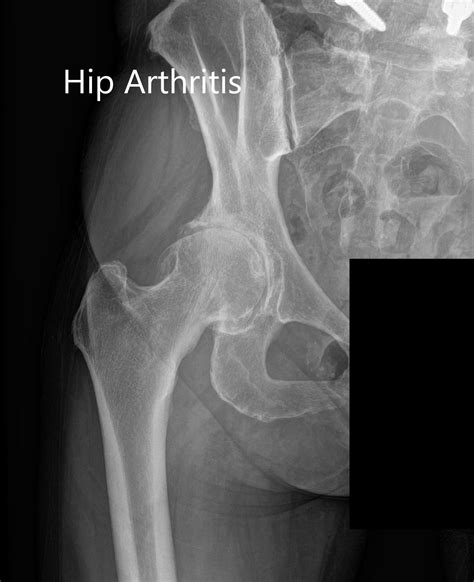

Common Conditions Detected by a Hip X Ray

A Normal Hip X Ray helps in identifying various conditions. Some of the most common include:

• Arthritis: Narrowing of the joint space and bone spurs.